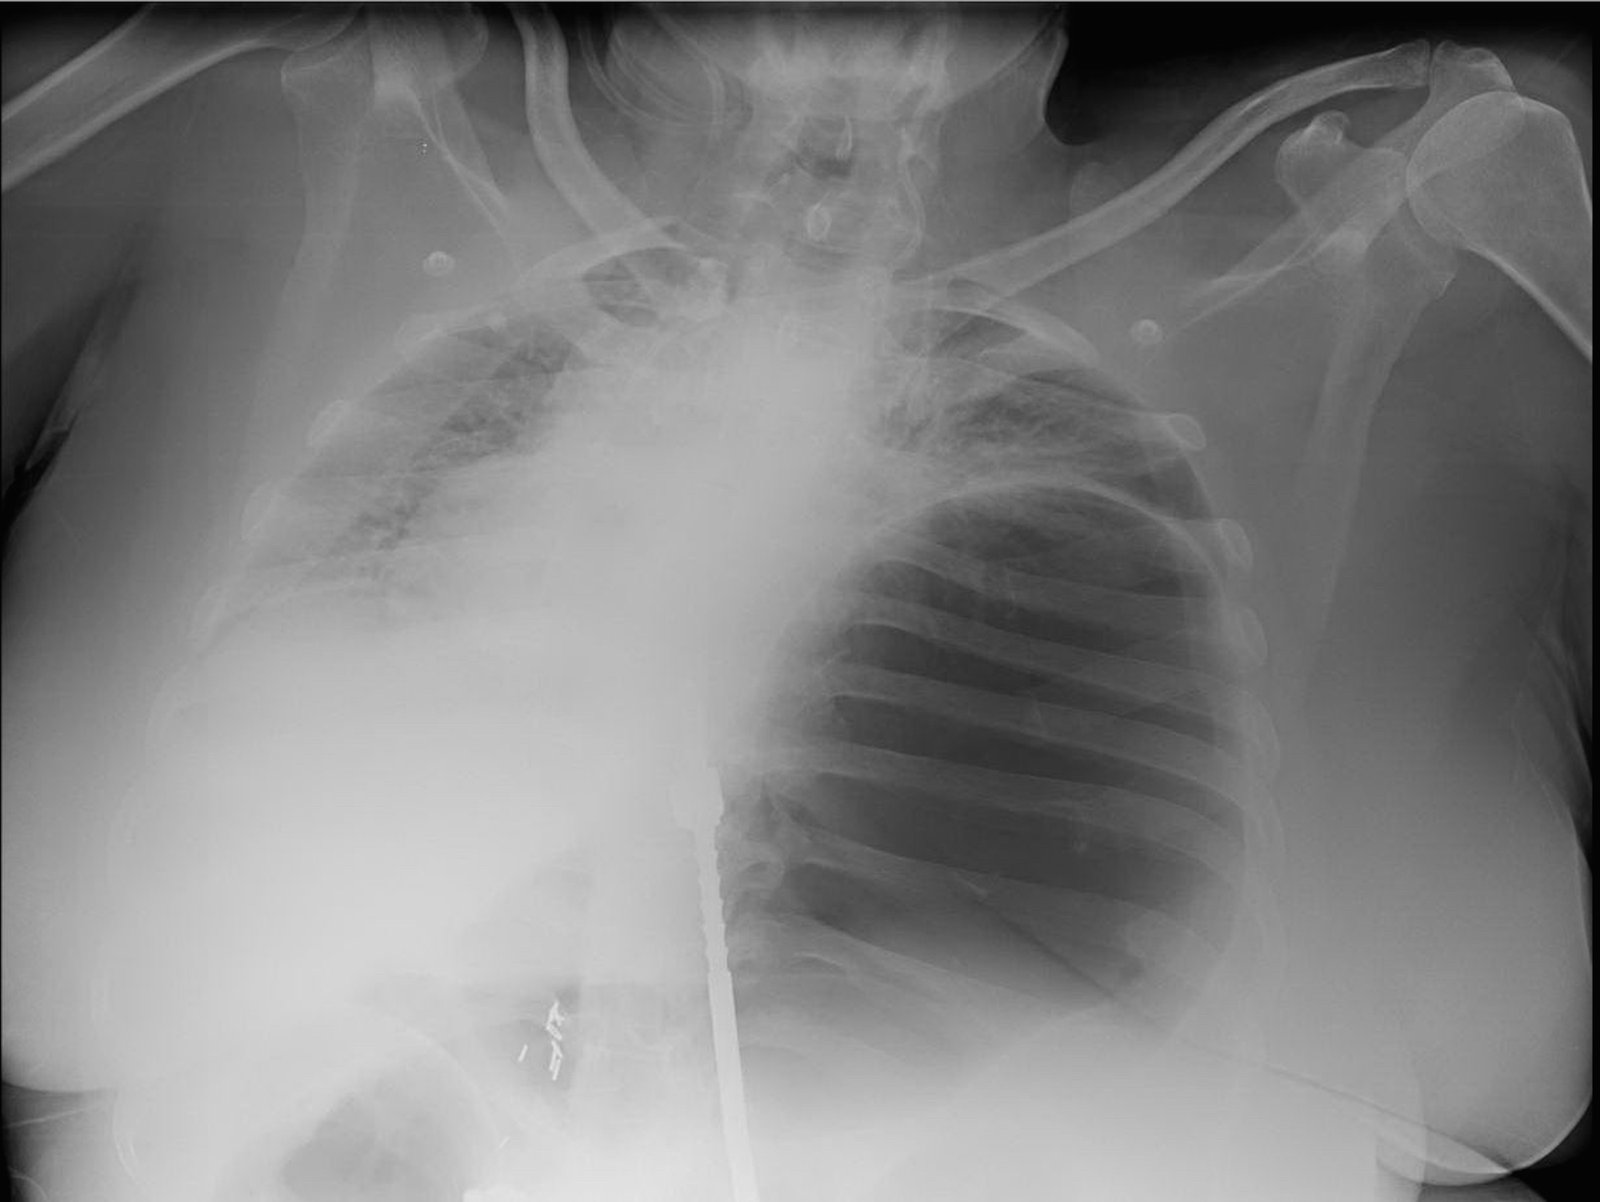

A 55-year-old female presented via transfer from a referring hospital with 48 hours of abdominal pain, vomiting and dyspnea. She was found to be in severe distress. Her temperature was 37.5°C, heart rate 130 beats per minute, respiratory rate 47 breaths per minute, blood pressure 80/48 mmHg, and oxygen saturation of 95% on a non-rebreather mask. She had distended neck veins, diminished breath sounds on the left hemi-thorax, and a distended abdomen. A chest x-ray that had been obtained at the referring hospital was immediately reviewed. The decision was made to intubate the patient. Following intubation, a nasogastric tube was placed with marked improvement in her hemodynamics. An abdomen-pelvis CT was obtained which showed a para-esophageal hernia with the majority of the stomach located in the left hemi-thorax and evidence of a bowel obstruction.

Radiography shows a dilated, gas-filled structure that fills nearly the entire left hemi-thorax. Lung markings are visible in the uppermost portion of the left hemi-thorax. There is mediastinal shift to the right. In the visualized portion of the abdomen, dilated loops of bowel are also visualized. This constellation of findings is consistent with a tension gastrothorax.